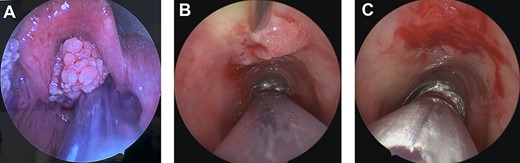

Intraoperative images. (A) Large, supraglottic, papillomatous lesion extending to petiole—excised at first surgery. (B) Tracheal papilloma being injected with Cidofovir at the base of lesion during second procedure. (C) Tracheal papilloma post debridement and injection of Cidofovir during the second procedure.

Two weeks later, he underwent a repeat microlaryngoscopy, tracheoscopy and debridement of tracheal papillomata with adjuvant cidofovir injection. The lesions treated were on the tracheal mucosa overlying the inferior aspect of the anterior cricoid and the left laryngeal ventricle (Fig. 1B and C). Four weeks later, an endoscopic septectomy, bilateral medial maxillectomy, right sphenoethmoidectomy and right sphenopalatine artery ligation were performed to eradicate sinonasal disease.